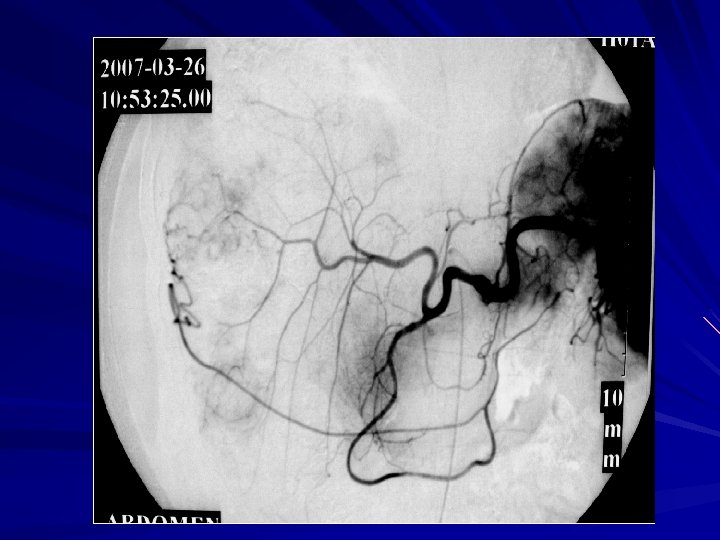

Use of micro-catheter—first TACE

Use of micro-catheter— 2 nd TACE -----OA branches involved in blood supply-----

Discussion -3 3、 Superselective Intervention OA lumen small、 tortuous,their average diameter was only 23 mm,normal angiography usually was not obvious. When parasitic OA blood supply, the diameter may be significantly enlarged. Using the microcatheter will help improving the success of OA superselective catheterization. In this group of cases OA superselective catheterization success rate was 63. 9%. Reasons of superselective failure:OA was too fine;sharp angular between branch and the trunk;multi-cluster support OA was invaded so plexiform.